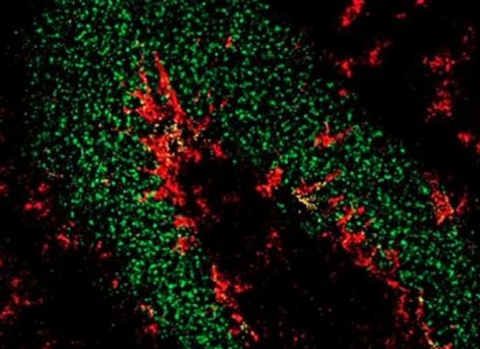

La plasticidad neuronal, también conocida como neuroplasticidad, es la capacidad del cerebro para cambiar su estructura y función en respuesta a la actividad y las experiencias. Este proceso incluye la formación de nuevas conexiones sinápticas, la modificación de las existentes y, en algunos casos, la generación de nuevas neuronas.

- Sinaptogénesis: Formación de nuevas sinapsis entre neuronas, esencial para el aprendizaje y la memoria.

- Neurogénesis: Proceso de generación de nuevas neuronas, más común en ciertas áreas del cerebro como el hipocampo.

El aprendizaje es uno de los principales motores de la plasticidad neuronal. Cada vez que aprendemos algo nuevo, se producen cambios en las conexiones neuronales que reflejan esta nueva información. Estos cambios pueden ser temporales o permanentes, dependiendo de la repetición y la importancia del aprendizaje.

- Potenciación a Largo Plazo (LTP): Un mecanismo clave en la plasticidad sináptica donde la transmisión de señales entre dos neuronas se fortalece con la actividad repetida. LTP es fundamental para la formación de recuerdos a largo plazo.

- Investigación en Neurogénesis: Estudios recientes han demostrado que la neurogénesis en el hipocampo está relacionada con la memoria y el aprendizaje espacial. Factores como el ejercicio físico y el entorno enriquecido pueden aumentar la neurogénesis.